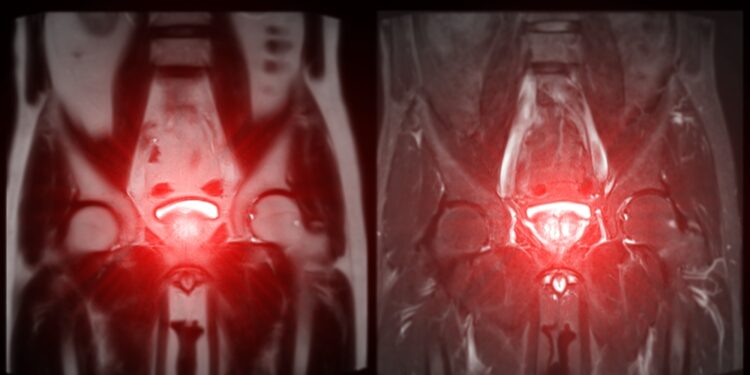

• Magnetinis rezonansas (MRT) – leidžia išsamiai įvertinti vidaus organus be rentgeno spindulių.